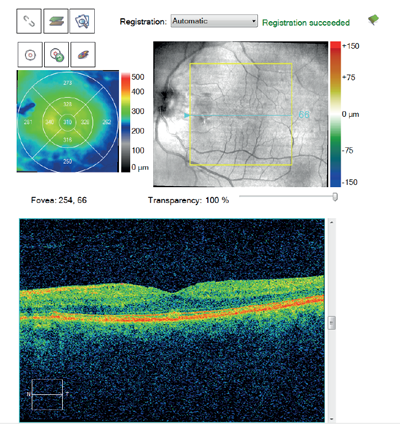

A 72-year-old gentleman presented for a follow-up appointment of a left ERM telling me that his eye felt considerably improved in terms of metamorphopsia. He had no relevant past ophthalmic history and no posterior vitreous detachment (PVD) was seen. Indeed, his BCVA showed an unusual improvement from 1.3 LogMAR at his last visit eight months before to 0.18 LogMAR when I saw him. Miraculously, on his OCT, the previous ERM (Figure 3a) had vanished (Figure 3b).

Figure 3b.

Figure 3: Macular change analysis OCT of the second patient shows a marked decrease in central retinal thickness

(b) as a result of spontaneous resolution of the ERM (a), possibly secondary to PVD.